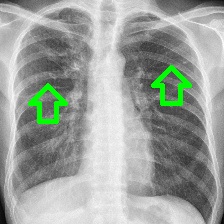

Figure 1: Overview of marginalization: (a) original with annotated mass (red box) before and after marginalization by our method; (b) local comparisons with popular methods (clockwise): original, blurring [9], inpainting (ours), and averaging [29]; (c) ROC curves of the mammography classifier (green curve) vs. healthy pixel inpainting only in healthy/pathological (blue/red curves) structures.

In contrast, reference based LE approaches directly manipulate the input image and analyze the resulting prediction’s differences [9]. They aim to assess an image-region’s influence on prediction by counterfactual reasoning: how would the prediction score vary, if the region’s image-information would be missing, i.e. its contribution marginalized? The prevailing heuristic approaches, e.g. Gaussian noise and blurring or replacement by a predefined colour [29, 8, 9], have been advanced to local neighborhood [31] and stronger conditional generative models [7, 28]. Reference based LEs have the advantage of an a-priori clear and intuitively conveyable meaning of their result, hence address informativeness for end-users. However, their applicability for medical imaging hinges on the utilized marginalization technique, i.e. the mapping between potentially pathological tissue representations and their healthy equivalent. Resulting prediction-neutral regions need to depict healthy tissue per definition. Contradictory, the presented approaches introduce noise and thereby possibly pathological indications or anatomically implausible tissue (cf. Fig. 1). Hence, they violate the needed faithfulness [9].

Thus, we computed ROC curves using the classifier on all test samples (i) without any inpainting as reference, and for comparison, randomly sampled inpainting (ii) only in healthy respective (iii) pathological scans over 10 runs (Fig. 1). The clear distance between the ROC curves of the mammography image classifiers without any inpainting, yielding an AUC of 0.89, and with inpainting in pathological regions, resulting in an AUC of 0.86, shows that the classifier is sensitive to changes around pathological regions of the image. Moreover, it is visible that the ROC curves of inpainting in healthy tissues with an AUC of 0.89 follow closely the unaffected classifier’s ROC curve (Fig. 1). The AUC scores for the TBC classifier without and with inpainting in healthy tissue are 0.89 and 0.88 which proves the above mentioned observations. Pathological tissue inpainting was ommitted in this case due to the lack of pixel-wise annotations.